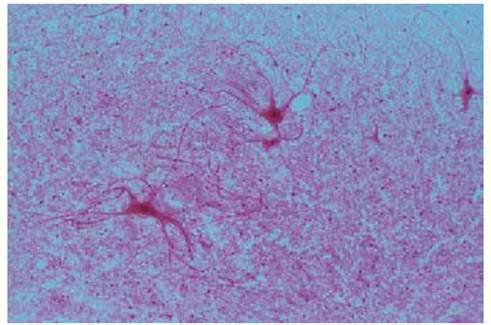

Multipolar Neurons

Anterior horn motor cells—i.e., motor neurons of the columnar anterior from the spinal cord— were obtained by careful maceration of the spinal cord and stained as a “squeeze preparation” (tissue spread out by gentle pressure). This technique makes it possible to preserve long stretches of the numerous long neuritis and make them visible after staining. In a tissue section, most of the cell processes would be sheared off. In this preparation, it is hardly possible to distinguish between axons (neuritis, axis cylinder) and the heavily branched dendrites. Axons extend from the nerve cell to the musculature and form synapses.

Figure: Multipolar Neurons